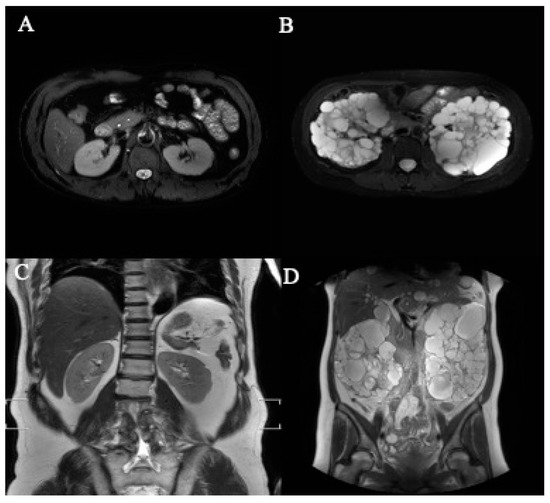

3.1. Images Collection